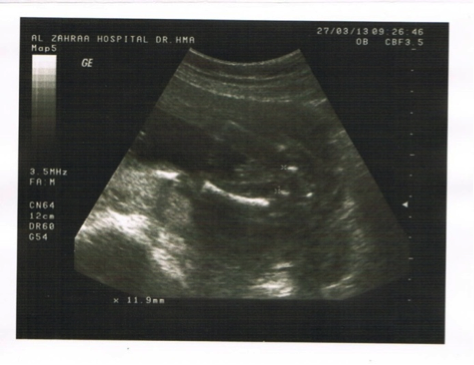

Ultrasound is an integral part of obstetric practice, and assessment of gestational age (GA) is a central element of obstetric ultrasonography. Sonographic estimation of GA is derived from calculations based on fetal measurements. Numerous equations for GA calculation from fetal biometry have been adopted in routine practice. This study reports a new method of estimating GA in the second and third trimester using interischial distance (IID), the distance between the two ischial primary ossification centers, on fetal ultrasound. Four hundred women with uncomplicated normal singleton pregnancies from 16 weeks to term were examined. Standard fetal obstetric ultrasound was done measuring biparietal diameter (BPD) and femur length (FL) for each fetus. The IID, in millimeters, was correlated with the GA in weeks based upon the BPD and FL individually, and the BPD and FL together. Statistical analysis showed strong correlation between the IID and GA calculated from the FL with correlation coefficient (r =0.989, P < 0.001). Strong linear correlation was also found between the IID and GA based upon BPD and BPD+FL. Further statistical analysis using regression equations also showed that the IID was slightly wider in female fetuses, but this difference was not statistically significant. Resulting from this analysis, we have arrived at an easy-to-use equation: GA Weeks = (IID mm + 8) ±1 week. We feel this method can be especially applicable in the developing world, where midwives may not have access to software for fetal biometry in their basic handheld ultrasound machines. Even more sophisticated machines may not come with loaded software for obstetrics analysis. There are several limitations to this study, discussed below. We recommend further studies correlating the IID with other biometric parameters.